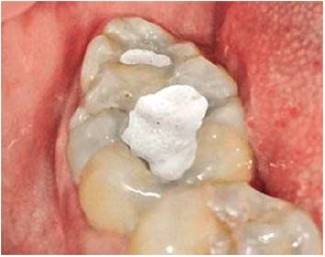

There might be cases when treatment should include orthodontic and oral rehabilitation with the aim of correcting dental malposition , improve occlusion, and esthetically characterize the tooth, mimicking and adjacent tooth’s morphology with the help of resin filling, veneers or crowns.22

If there are suitable clinical circumstances, these supernumerary teeth can also be treated by means of a root canal treatment, such was the case reported by Gomez Sosa, describing a 48 year old female patient with fused lower third molar and distomolar, treatment involved root canal and chamber erupted in a favorable position. In this case the patient was subjected to X-ray control and clinical examination every three months, during one year29(Figures 26 and 27).